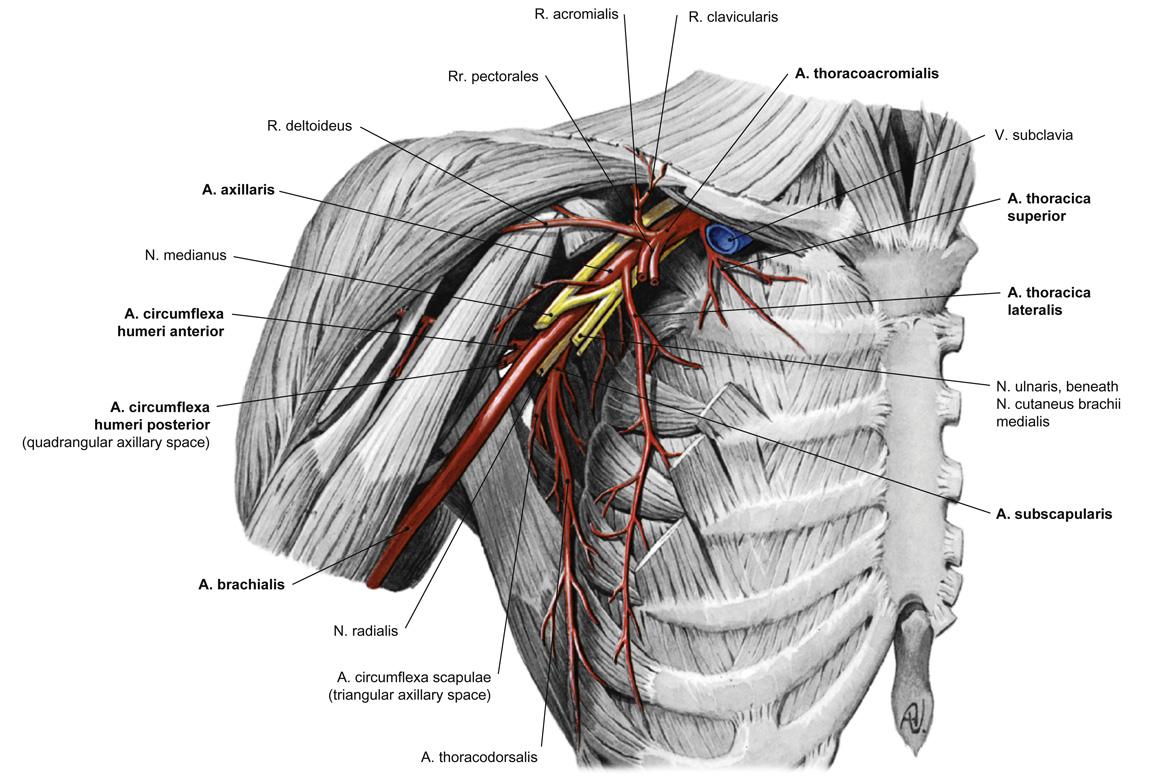

Fig 3.17: a. axillaris

-

scapula

-

humerus

tuberculum maius tuberculum minus crista tuberculi maioris crista tuberculi minoris collum chirurgicum

m pectoralis minor (geel) m pectoralis maior (geel) a thoracoacromialis a thoracica lateralis -

a subscapularis

a cx. scapulae a thoracodorsalis

a cx. humeri posterior (samen met n. axillaris door laterale okselpoort) a cx. humeri anterior a brachialis (vanaf onderrand m. pectoralis maior)

|